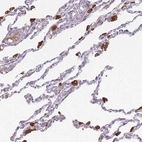

Immunohistochemical staining of human lung shows strong cytoplasmic positivity in macrophages.